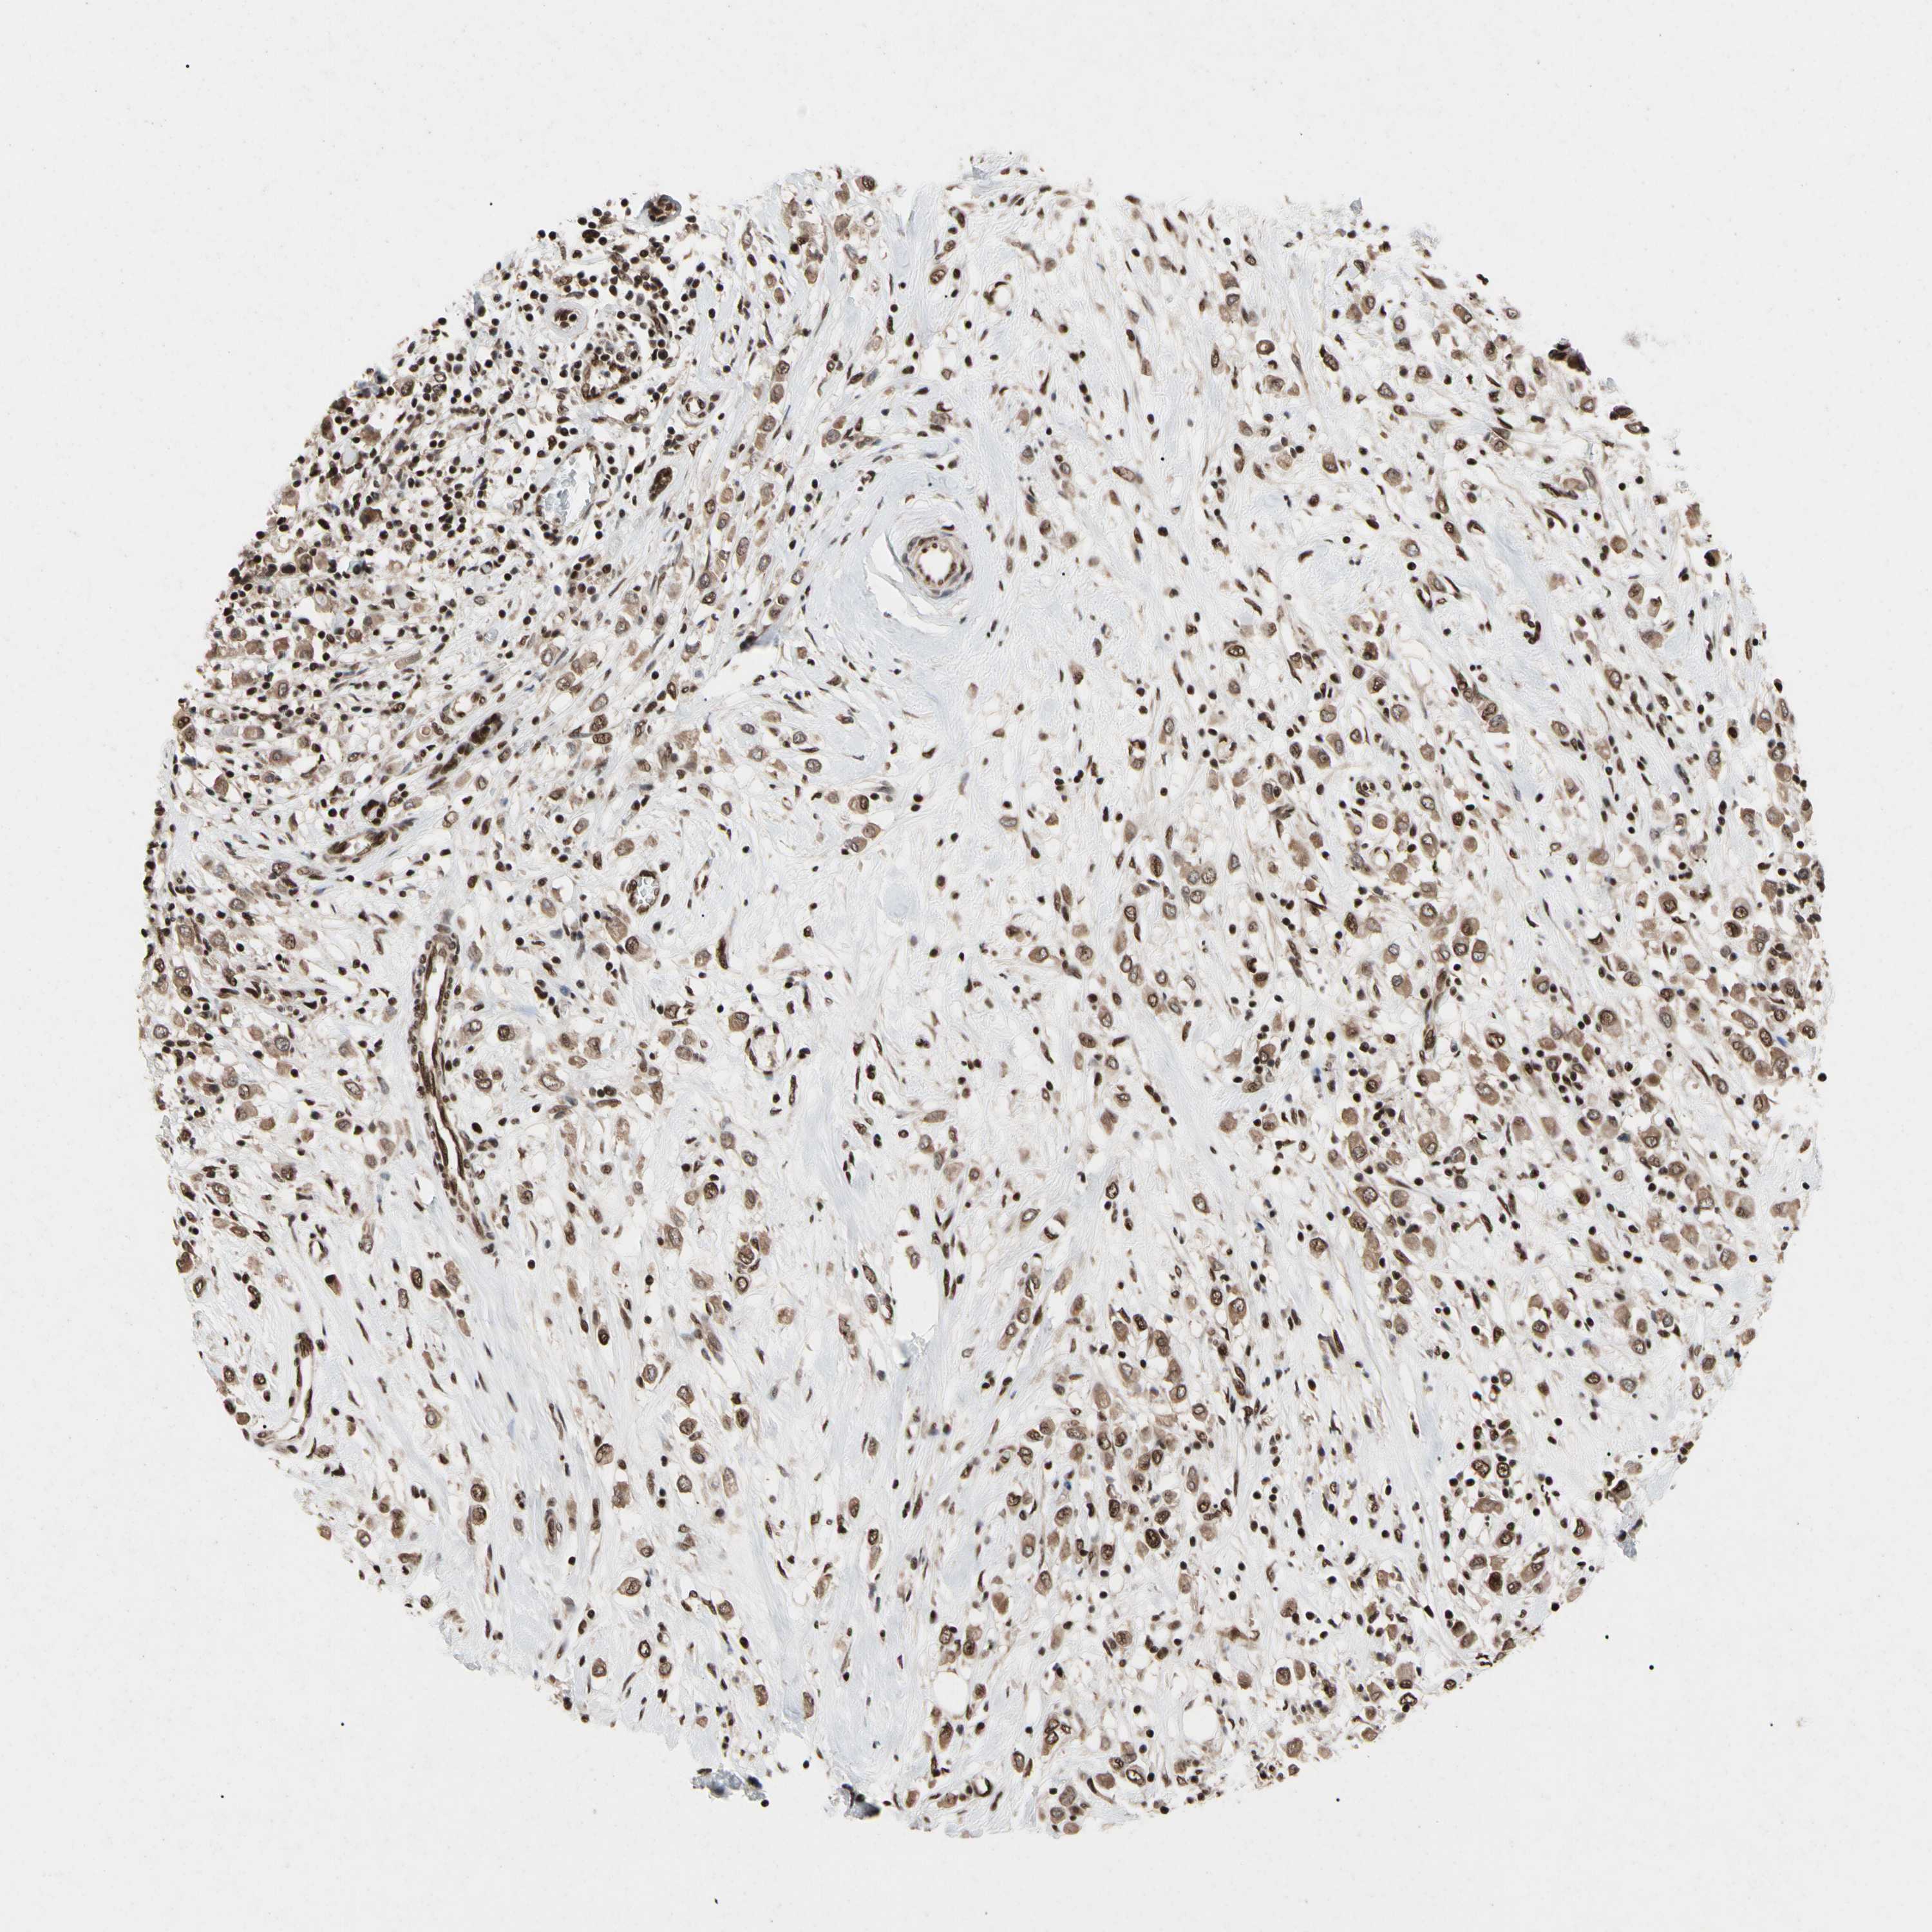

BRCA TCGA BRCA VALIDATION PROTEIN EXPRESSION

Breast cancer

Human cancer